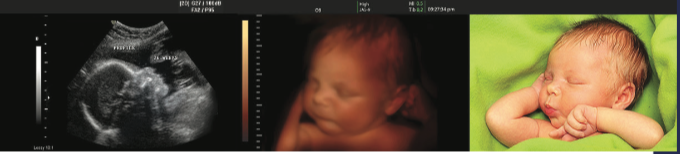

Your local Knights of Columbus are raising money toward the purchase of ultrasound machines for qualified pregnancy centers in the Cleveland Diocese, with matching grants from the Knights' Culture of Life Fund.

Ultrasound technology has proven to be one of the most effective tools to empower women with crisis pregnancies to choose life.